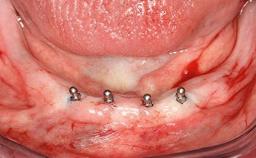

In 2007, a 97-year-old patient presented for treatment at the Geneva Dental School. His dentist had retired. Like many elderly patients, he was left without regular dental care. He lived on a geriatric ward, as he was partly dependent on help with most of the activities of daily living (ADL), such as getting dressed, washing, taking a shower, or climbing stairs. However, he was able to go to the bathroom and get up from bed on his own (ADL score 80, min. 18, max. 126; a low score signifies a high degree of dependency) (Lawton and Brody 1969). He was not bound to a wheelchair, but used a walker. Moreover, he was socially highly active—his family visited on a regular basis and he often went to the restaurant with his friend, who was some 20 years younger. His cognitive function did not seem to be impaired in a normal conversation, although his MMSE score was only 21/30 at that time (Folstein and coworkers 1975). The patient was a retired pharmacist, and his latest passion was astronomy.

Case Type Edentulous Mandible

# of Implants 2

Type of Implants One-Piece

Defining Characteristics Fully edentulous lower jaw to be rehabilitated with two or more implants

Modality 2 interforaminal implants